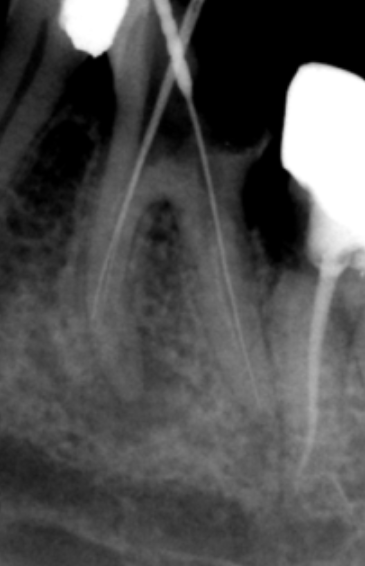

Technique fiable et reproductible, elle reste la méthode de référence. La méthode de Beveridge (1966) comprend deux étapes :

Analyse du cliché préopératoire : mesure approximative de la longueur radiculaire (LT estimée), facilitée par l’utilisation de grilles millimétrées radio-opaques.

Radiographie lime en place : instrument (lime K ou broche) amené à la LT estimée moins 0,5 ou 1 mm, permettant un ajustage précis de la mesure.

La Radiovisiographie (RVG)

La radiographie numérisée présente plusieurs avantages :

- Images de meilleure qualité

- Exploitation clinique facilitée

- Archivage simplifié

- Doses d’irradiation réduites

- Temps d’acquisition fortement diminué

- Variation de contraste pour mieux repérer les structures anatomiques